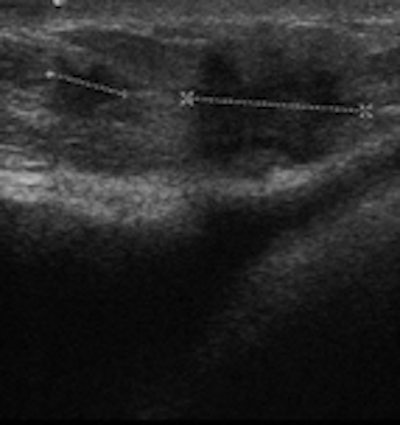

Conventional breast imaging techniques, especially ultrasound, still provide useful information about implants. However, intracapsular rupture, which is frequent but often clinically silent, cannot be easily detected by mammography because of the radiopacity of the implant. The sensitivity of ultrasound is greater if discontinuous echogenic lines within silicone gel ("stepladder sign") are detected. Periprosthetic hyperdensity on mammography and the "snowstorm sign" on ultrasonography are significantly associated with extracapsular rupture.